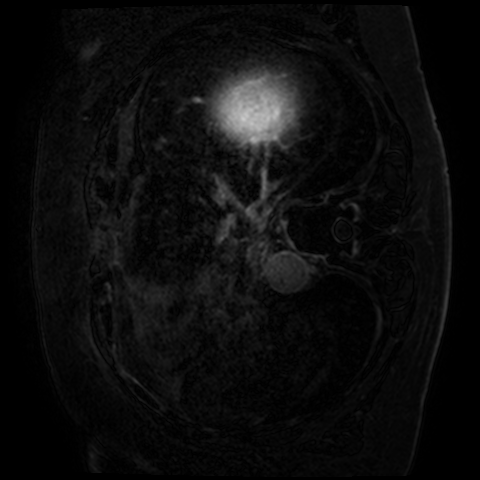

Late gadolinium enhancement magnetic resonance imaging (LGE-MRI) is typically used to provide quantitative information on atrial scars [25]. In this measurement, location and size in the left atrium (LA) indicate pathology (i.e., LA scars) and progression of atrial fibrillation [12].

Nowadays, deep learning models have been widely used to segment LA cavities and quantify LA scars from LGE-MRIs [3] to help radiologists with initial screening for quick pathology detection. Meanwhile, LGE-MRIs are often collected by multiple scanners and possibly in low imaging quality. Each of them produces inconsistent domain information [14], including different contrast and spatial resolutions. (1) Promoting the generalization of a segmentation model against domain inconsistency becomes another challenge.

The LAScarQS dataset includes two tasks: 1). LA and LA Scar segmentation (task 1), and 2). LA Segmentation across scanners (task 2). The first task contains 60 3D LGE-MRIs with labels containing LAs and LA scars, while the second consists of 130 3D LGE-MRIs from multiple medical centers with labels containing only LAs [12].